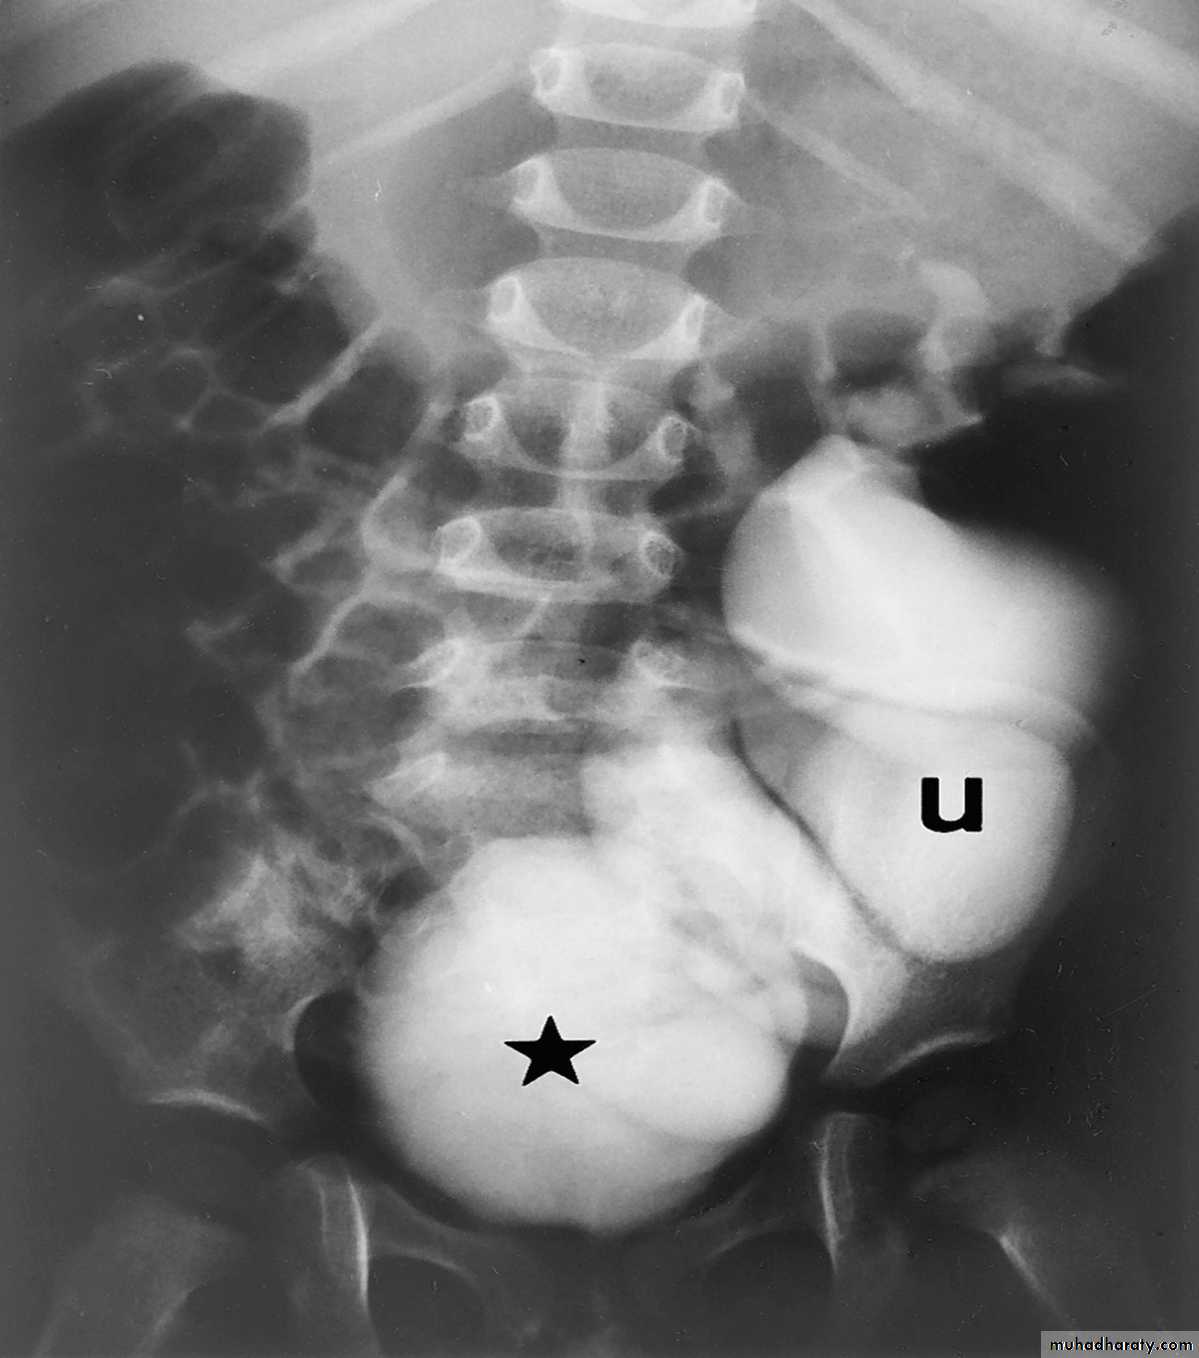

Horse shoe kidney -Kidneys may fail to separate.

-Almost invariably the lower poles remain fused.

-The kidneys axes are more parallel to the spine and malrotated.

IVU shows

1. The kidneys at low position .

2.Close to the spine with long axis parallel to the spine .

3. Malrotation manifested by medially directed calyces.

4- The renal pelvis and ureters are anterior and lateral in position .